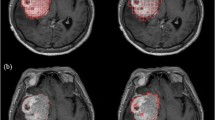

The first step to apply any morphometric analyses on the neoplastic angio-space is the choice of the technique to visualize the microvessels and the following image analysis, which should be standardized (see Chap. 12) (Fig. 24.1).

When the target of analysis is the microvascular network, several issues have to be considered, for example, whether the analysis is performed on the basis of the space-filling area of the vessels or on skeletonized representations of the microvessels.

In the image analysis, eventual artifacts related to the segmentation of immunoreactive vessels have to be considered. For example, nonspecific immunoreactivity can limit the automatic detection of the vessels, as in the case when antigens diffuse to other compartments (e.g., CD34 antigens which immunostain cell nuclei or necrotic areas rather than endothelial cells). In such cases, a pathologist is still required to identify any artifacts, which should be eliminated from the analysis.

Other digital image acquisition calibration parameters should be standardized as well, in terms of regulating the light intensity of the microscope, maintaining the same resolution over the whole series, and using an identical threshold to extract the immunoreactive vessels. A virtual microscope can be used to digitize the entire specimen rather than few areas selected manually. The vessels can be extracted as a whole from the specimen and organized in a vascular catalog, giving a snapshot on the number and shape of the microvessels within the specimen (Fig. 24.2).

Computer-aided technique for fractal analysis of the microvasculature in histological specimens. Estimation of the morphometric fractal parameter in the whole section and in the hot spot region of specimens of brain gliomas; detection of microvessels using antibodies raised against CD34. The extraction of the whole specimen and the segmentation of the immunoreactive vessels (a, b) allow the automatic measurement of the morphometric parameters listed in Table 24.4. Moreover, a grid of boxes measuring 1 mm to a side length is superimposed on the whole histological section. For each box, the ratio between the local vascular area and the local neoplastic area is calculated [local A(%)]; the box with the highest local A(%) is automatically selected and extracted to be used as the “hot spot” representative of the whole specimen (c). (d) Hot spot of the specimen, automatically extracted. (e) Selection of the RGB threshold to automatically extract the CD34+ vessels. (f) Box-counting method: superimposition on the image of grids with boxes of different lengths, from a minimum size (ε min ) to a maximum size (ε max ), in the preselected scaling window. (g) A monofractal behavior was found by limiting the scaling window to a range of two orders of magnitude (ε min = 1 μm – ε max = 100 μm). The slope of the obtained curve is the microvascular fractal dimension (mvFD) [Axes of the log-log graph (box-counting method): X-axis = Box size (mm); Y-axis = N Boxes]. (h) Considering that a maximum size of the box of 100 μm does not cover the complete hot spot, a wider scaling window was also applied (Reproduced from Di Ieva et al. [20])